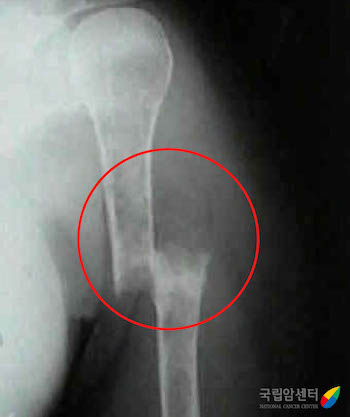

[ 다발골수종 환자에서 발생한 위팔뼈의 골절(X ray) ]

다발골수종은 환자들마다 증상의 차이가 있으나 가장 흔한 대표적인 증상으로는 빈혈, 뼈 통증, 신장 수치 상승, 및 고칼슘 혈증이 있습니다. 빈혈은 다발골수종의 원인이 되는 형질세포의 골수 내 증식에 의하며 이로 인한 피로감, 어지러움 및 호흡 곤란 등의 증상이 발생할 수 있습니다. 뼈의 통증 및 골절 역시 다발골수종의 가장 흔한 증상 중의 하나이며 특히 척추뼈의 압박 골절이 발생하는 경우 허리 통증 외에도 하지 마비 등의 신경학적 증상이 동반될 수 있습니다. 고칼슘 혈증으로 인한 구역감, 변비, 의식 및 정서 상태의 변화가 유발될 수 있으며, 신장 기능 저하로 인한 혈액 검사상 신장 수치의 상승 및 단백뇨가 발생할 수 있습니다. 또한 면역 기능의 저하로 인한 감염 증상 및 응고 인자 기능 저하로 인한 출혈 증상도 다발골수종에서 보일 수 있는 증상에 속합니다.

다발골수종은 환자들마다 증상의 차이가 있으나 가장 흔한 대표적인 증상으로는 빈혈, 뼈 통증, 신장 수치 상승 및 고칼슘 혈증이 있습니다. 빈혈은 다발골수종의 원인이 되는 형질세포의 골수 내 증식에 의하며 이로 인한 피로감, 어지러움 및 호흡 곤란 등의 증상이 발생할 수 있습니다. 뼈의 통증 및 골절 역시 다발골수종의 가장 흔한 증상 중의 하나이며 특히 척추뼈의 압박 골절이 발생하는 경우 허리 통증 외에도 하지 마비 등의 신경학적 증상이 동반될 수 있습니다. 고칼슘 혈증으로 인한 구역감, 변비, 의식 및 정서 상태의 변화가 유발될 수 있으며, 신장 기능 저하로 인한 혈액 검사상 신장 수치의 상승 및 단백뇨가 발생할 수 있습니다. 또한 면역 기능의 저하로 인한 감염 증상 및 응고 인자 기능 저하로 인한 출혈 증상도 다발골수종에서 보일 수 있는 증상에 속합니다.

다발골수종 환자의 가장 흔한 증상은 허리 통증이나 갈비뼈의 통증입니다. 이 통증은 파골세포(osteoclast)가 뼈 조직을 파괴하여 생기는데 안정 시에는 경미하지만 움직일 때는 통증이 심하고 아픈 부위가 이동하는 것이 특징입니다. 통증이 계속되면 병적 골절의 가능성도 염두에 두어야 합니다. 또 뼈 조직이 파괴되어 칼슘이 혈액으로 과도하게 방출되면 심한 고칼슘 혈증이 일어납니다. 칼슘 농도가 높아지면서 심각한 탈수, 피로, 무력감, 입맛의 소실, 구갈, 의식 저하 등의 현상이 나타날 수 있고, 심장 및 신장에 피해를 줄 수 있습니다.